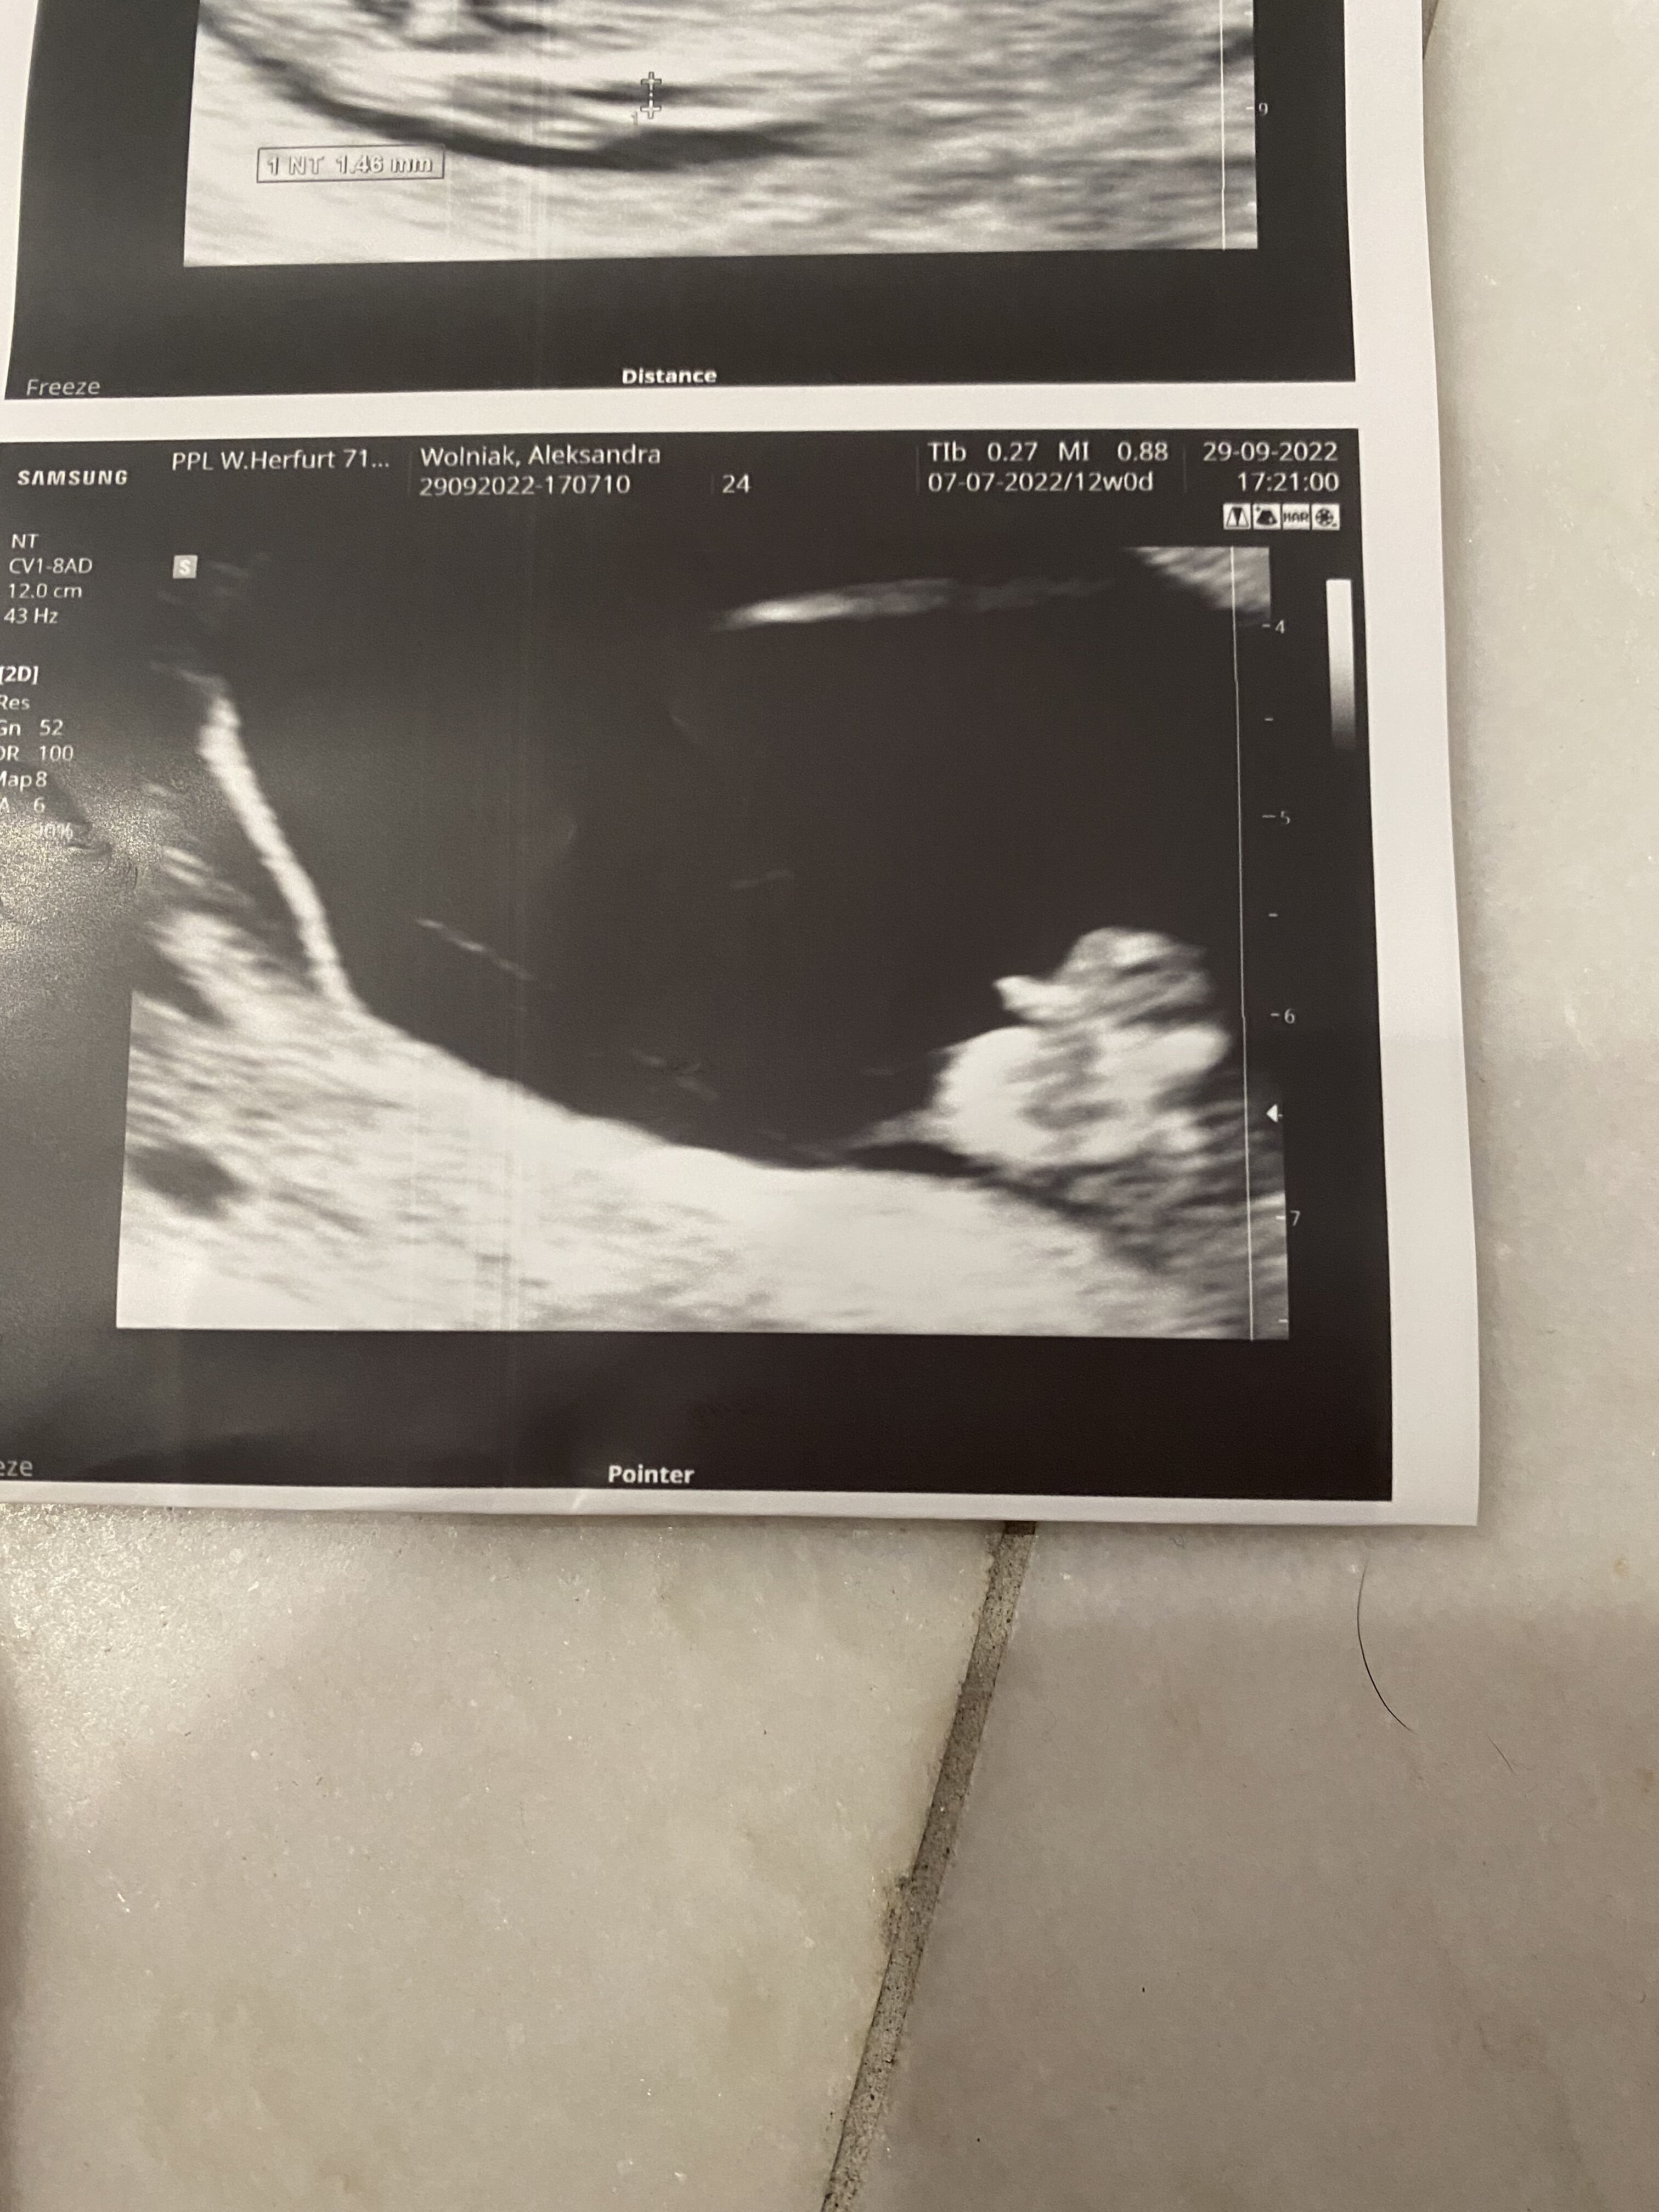

Co sądzicie? Lekarz mówi ze raczej chłopak a ja liczę na córcię bo chłopaka już mam :) i szczerze mówiąc ja siusiaka nie widzę.. A Wy? Teraz jestem w 20tc